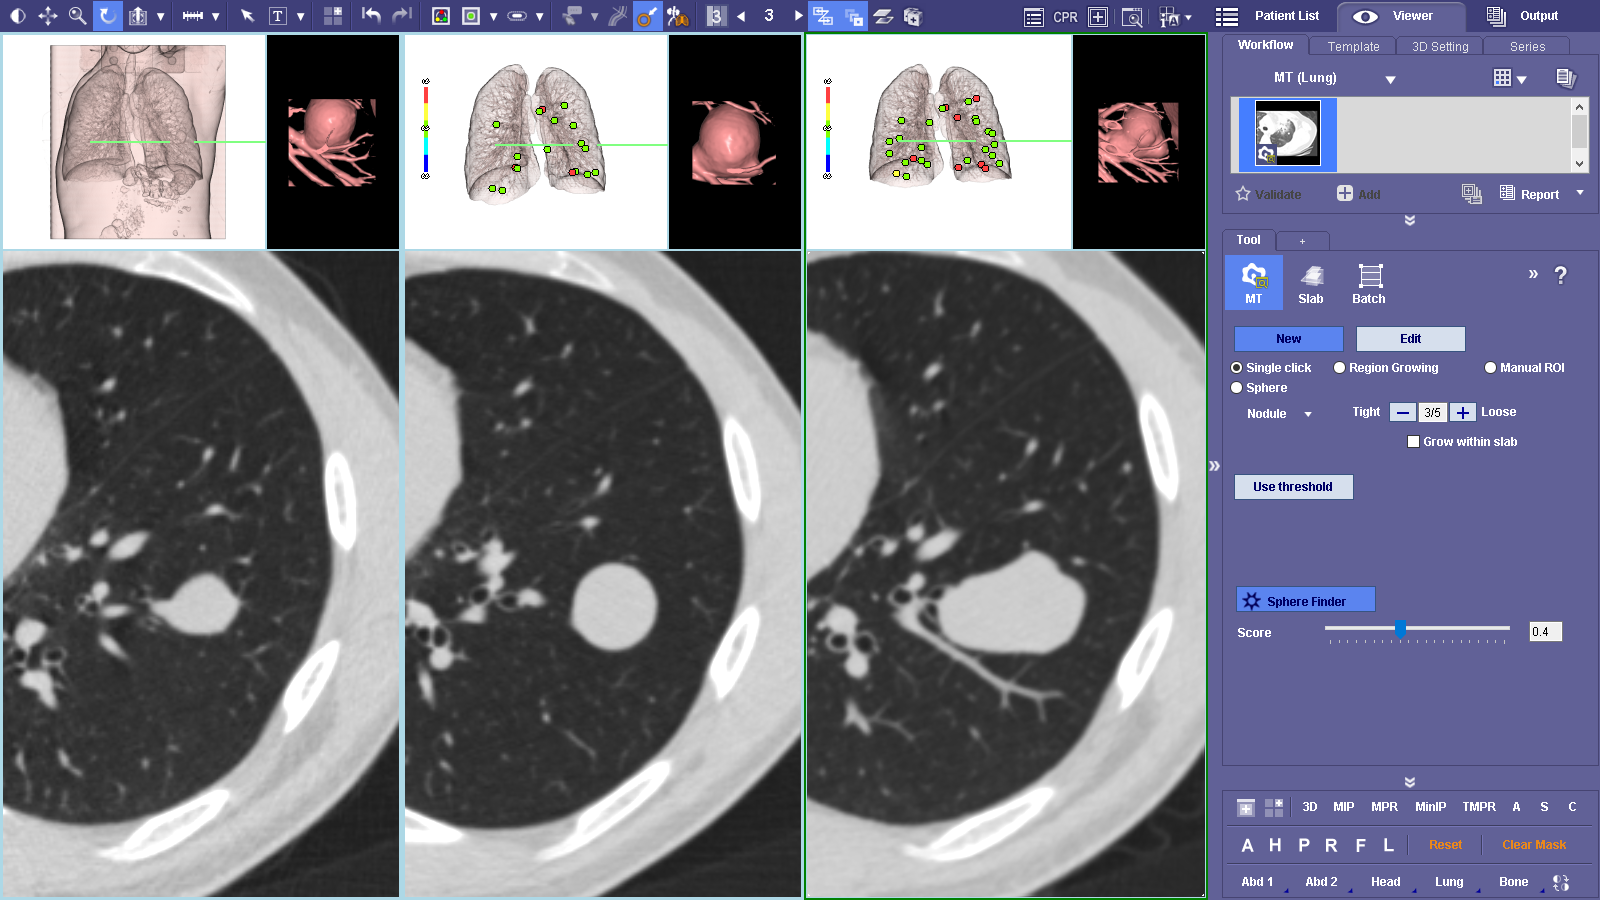

MT Lung workflow is a comprehensive lung analysis tool used to segment, analyze and track lung lesions over the course of time. SphereFinder allows a second look as the software helps identify spherical areas of interest. The Findings Viewer aids in tracking, classifying and measuring confirmed areas of interest. The Measurement Tracking feature tracks confirmed measurements over time.

MT Lung workflow is a comprehensive lung analysis tool used to segment, analyze and track lung lesions over the course of time. SphereFinder allows a second look as the software helps identify spherical areas of interest. The Findings Viewer aids in tracking, classifying and measuring confirmed areas of interest. The Measurement Tracking feature tracks confirmed measurements over time.

Supporta criteri come LRADS®1/01 Le misurazioni e le classificazioni vengono visualizzate su Findings Viewer.